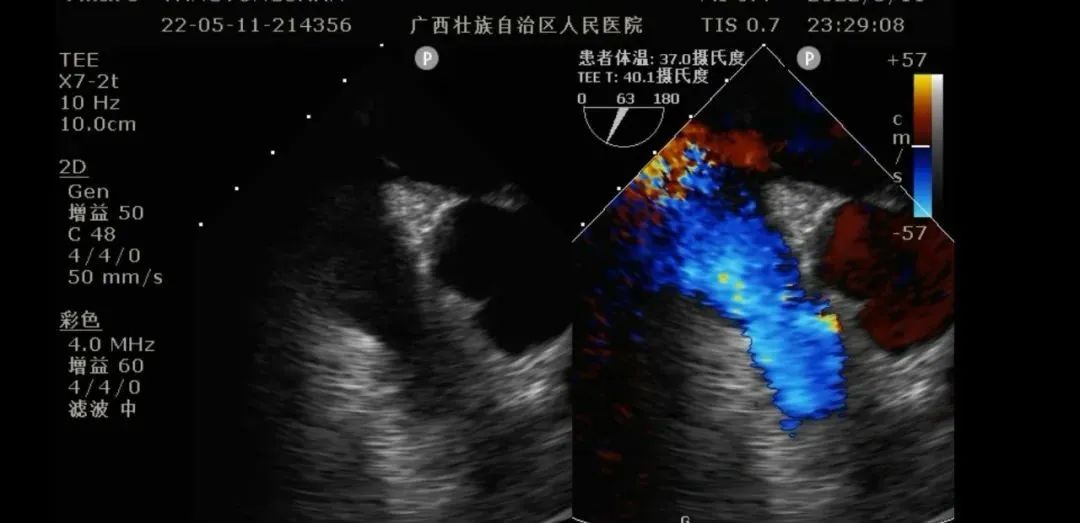

食道超声引导下进行Crescent置管及定位:

食道超声定位ECMO血流